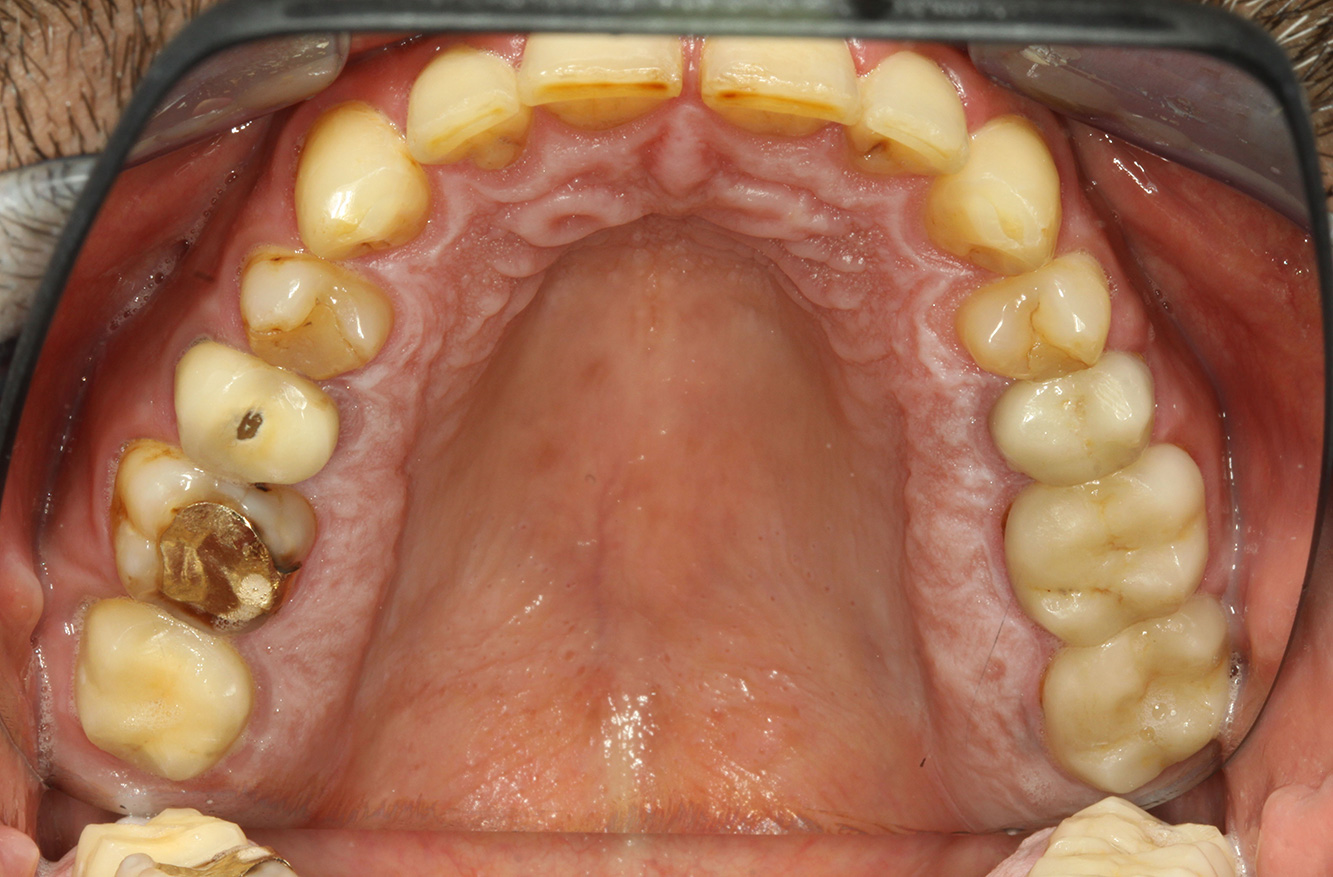

The endocarditis patient with active caries lesions*

The patient is 39 years old and has previously undergone aortic valve replacement due to valve failure and endocarditis. ASS 100 is taken regularly as an anticoagulant. In terms of lifestyle, the patient’s diet is classified as caries-promoting due to the regular consumption of sugary foods and the fact that six to seven meals are consumed daily. The patient’s oral health indicates a moderate risk of caries, with active lesions. The risk of periodontitis is low, but gingivitis is present. The following recommendations are made for prophylactic treatment.

Due to the active caries lesions and the associated risk of progression, a shortened recall interval of three to four months is recommended.